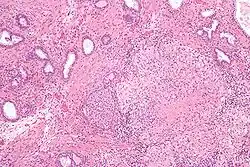

![]() Microscopic image of the Calmette–Guérin bacillus, Ziehl–Neelsen stain, magnification: 1,000nn | |